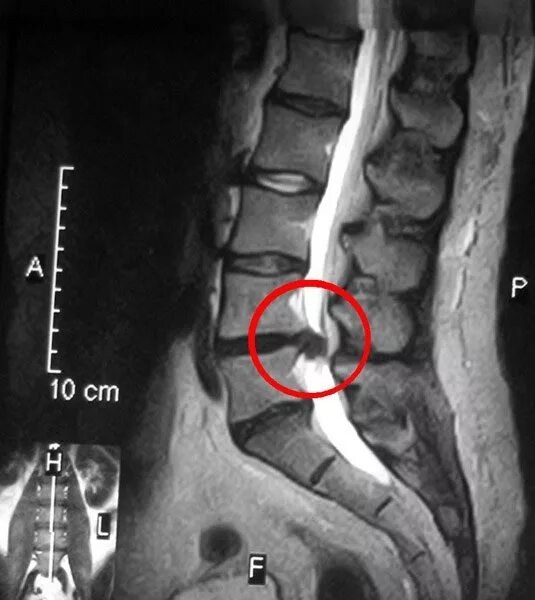

Грыжа 4 5